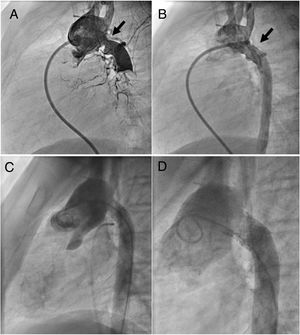

Intentional fracturingIntentional fracturing of the implanted stent was performed in 7 patients (figure 3; table 4). In each case, a second stent was implanted before fracturing to avoid napkin-ring formation and to stabilize the vessel wall. No patient has required reoperation to date. No spontaneous stent fracture was detected during follow-up.

Patient with hypoplastic left heart syndrome after the Norwood procedure who developed significant narrowing following complex aortic arch reconstruction at 8.2 months of age and 5.2kg body weight (A, arrow). This patient was treated with a 6-mm Formula stent (B, arrow). The same patient, more than 11 years later, was scheduled for intentional stent fracturing (C, weight 49kg); successful intentional stent fracturing was performed after implantation of an EV3 Mega LD stent (D).

| 4 | 8.2 | 5.2 | Formula | 6.0 | 5 | 140.7 | 49.0 | Mega LD | Atlas | 14 |